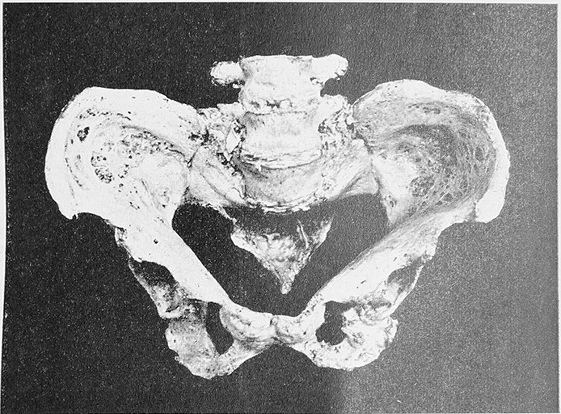

На лѣченіи остеомалакіи я не считаю нужнымъ подробно останавливаться, такъ какъ ему отводится достаточно мѣста въ учебникахъ и подробное изложеніе его вывело бы меня изъ рамокъ этой статьи. Теперь я перехожу къ описанію таза больной, страдавшей остеомалакіей но, къ сожаленію, я ему могу предпослать лишь весьма неполный анамнезъ.

Тазъ этотъ принадлежитъ женщинѣ изъ превилигированнаго сословія, родившейся въ Петербургѣ, жившей постоянно здѣсь и умершей на 50 году жизни послѣ приблизительно 13 лѣтней болѣзни. Въ молодости она была совершенно здорова и во время своего замужества рожала безъ особенныхъ затрудненій. Болѣзнь началась въ 1883 г. тянущими болями въ костяхъ. Пользовавшему ее врачу уже тогда бросилось въ глаза, что больная совершенно особеннымъ образомъ стоитъ на ногахъ, при чемъ раздвигаетъ ихъ, какъ бы ища болѣе твердой опоры. 5 Октября 1885 г. больная дома упала на полъ и получила переломъ праваго бедра въ средней трети. Она поступила въ городскую Петропавловскую больницу, гдѣ ей наложена была гипсовая повязка. Когда черезъ 2 мѣсяца повязка была снята, то оказалось, что кость не срослась, а образовался ложный суставъ. Мазоль не образовалась и послѣ того, какъ подъ наркозомъ сдѣлано было растираніе концовъ перелома другъ о дружкѣ, и больная черезъ 9 мѣсяцевъ была выписана изъ больницы съ ложнымъ суставомъ, снабженая Тііотав’овымъ аппаратомъ. Дома боли въ разныхъ костяхъ уже не оставляли больную и, наконецъ, она вынуждена была слечь въ постель. Въ началѣ января 1887 года появились особенно сильныя боли въ правой ключицѣ, которая припухла, стала мягкой и, когда припуханіе исчезло, осталось искривленіе кости. Въ серединѣ января 1887 г. начала сильно болѣть лѣвая нога и послѣ неловкаго движенія, произведеннаго въ лежачемъ положеніи, вдругъ появилась припухлость и сильная чувствительность бедра, что заставило больную вновь поступить въ больницу (19 января 1887 г.). При поступленіи отмѣчены укороченіе лѣваго бедра, въ верхней трети его, припухлость и ненормальная подвижность кости. Кровоизліянія и крепитаціи нельзя было опредѣлить. Во все время пребыванія въ больницѣ, т. е. въ теченіи 10 лѣтъ и 76 дней, больная уже не оставляла постели. Боли въ костяхъ покидали ее только по временамъ, иногда онѣ появлялись съ большей силой въ отдѣльныхъ костяхъ; обыкновенно вслѣдъ за этимъ обнаруживалось легкое припуханіе кости, которая становилась мягче и гибче и, наконецъ, дѣло кончилось искривленіемъ или самопроизвольнымъ переломомъ. Въ послѣднее время, за исключеніемъ черепа и плечевыхъ костей, на скелетѣ уже не было такой кости, которая бы тѣмъ или другимъ образомъ не была измѣнена. Особенно рѣзкими были обезображенія на лѣвой нижней конечности и на грудной клѣткѣ, какъ это видно на фотографическомъ рисункѣ, снятомъ А. JE- Вуколовьгмъ съ больной послѣ смерти (рис. 1). Мучительному существованію больной положилъ конец

Рис. 1

Рис. 2

острый катарръ кипіекъ. Слѣдуетъ еще упомянуть, что, не смотря на долголѣтнее лежаніе на спинѣ, больная никогда не страдала пролежемъ.

Вскрытіе, сдѣланное II. Е. Делакроа, дало слѣдующій пата- лого-анатомическій діагнозъ. Osteomalakia. Hepar adiposum et muschatum. Cholelithiasis. Nephrolithiasis et Nephritis chronica parenchymatosa dextra. Pyelitis suppurativa sinistra. Atrophia re- nis sinistri. Cystitis suppurativa. Colitis acuta catarrhalis.

Тазъ и правая бедренная кость, вынутые изъ трупа, оставлены для патологическаго музея больницы.

Такъ какъ больная, благодаря перелому бедра, въ сравнительно раннемъ періодѣ болѣзни была уже прикована къ постели, то измѣненія въ тазу (рис. 2) не столь значительны, какъ можно было-бы ожидать въ виду далеко ушедшаго общаго заболѣванія. Тяжесть тѣла могла оказать свое дѣйствіе только на сравнительно мало измѣненную кость; впослѣдствіи, когда измѣненія въ костяхъ уже достигли высокихъ степеней, недоставало, вслѣдствіе постояннаго лежанія на спинѣ, того момента, который главнымъ образомъ обусловливаетъ обезображенія скелета. Тѣмъ не менѣе измѣненія въ тазу вполнѣ характерны для остеомалакіи.

Крестцовая кость узка. Общая ширина ея равняется у основанія 10,3 стм., въ самомъ широкомъ мѣстѣ на уровнѣ безъимянной линіи 12,0 стм. Длина крестца, благодаря тому, что онъ согнутъ подъ острымъ угломъ, значительно уменьшена; она равняется до загиба 6,5 стм., а отъ загиба до копчика 3,5 сантим. Благодаря загибу, который находится въ области 3-го крестцоваго позвонка, крестецъ и еще болѣе верхушка копчика значительно приближены къ мысу, при чемъ послѣдняя лежитъ на линіи, соединяющей обѣ spinae ischii, заходя за нее кпереди еще на 1 стм. Разстояніе отъ мыса края основанія крестцовой кости до верхушки крестца равняется 6,7 стм., а до верхушки копчика 6,4 стм. Верхняя половина крестцовой кости сильно наклонена. Тѣла крестцовыхъ позвонковъ выдаются впередъ нѣсколько сильнѣе крыльевъ. На крыльяхъ перваго позвонка съ обѣихъ сторонъ замѣчается по бороздѣ, которая идетъ отъ тѣла крестца къ синхондрозу и отчасти еще заходитъ на лопасти подвздошныхъ костей, являяся выраженіемъ низдавленія тѣла перваго крестцоваго позвонка по направленію внизъ и впередъ. Вообще вся крестцовая кость какъ будто немного смѣщена книзу и кпереди; это можно заключать изъ того, что поперечные отростки 4-го поясничнаго позвонка стоятъ на одномъ уровнѣ съ гребнемъ подвздошной кости, а потому 5-й поясничный позвонокъ стоитъ гораздо ниже, чѣмъ это бываетъ при нормальныхъ условіяхъ; затѣмъ еще изъ того, что facies auriculares подвздошныхъ костей въ верхней своей части лежатъ на небольшомъ пространствѣ свободными. Весьма небольшихъ размѣровъ та часть крестца, которая лежитъ подъ загибомъ и соотвѣтствуетъ 4-му и 5-му крестцовымъ позвонкамъ. На задней поверхности крестецъ имѣетъ нормальные отростки, только слабѣе выраженные, и потому представляется уплощеннымъ.

Лопасти подвздошныхъ костей малы въ сравненіи съ нормальнымъ тазомъ; вслѣдствіе атрофіи костнаго вещества образовались на поверхности ихъ многочисленные дефекты большей или меньшей величины, благодаря чему лопасти просвѣчиваютъ въ видѣ рѣшета. Отъ передней поверхности крестцово-подвздошнаго сочлененія идетъ къ передней части гребня вышеупомянутая борозда. Spinae posteriores сближены другъ къ другу; разстояніе между ними равняется 5,8 стм. Въ области лонно-подвздошныхъ бугорковъ (tubercula ileo-pubica) костный край смѣщенъ впередъ и внизъ, такъ что получается впечатлѣніе, будто эта часть таза сползла внизъ. Разстояніе между бугорками равняется 10,8 стм. Вертлужныя впадины больше смотрятъ впередъ, чѣмъ при нормальныхъ условіяхъ. Лонное срощеніе нѣсколько выдается впередъ въ видѣ клюва и лежитъ не прямо противъ мыса, а нѣсколько правѣе. Нисходящая вѣтвь лонной кости и восходящая вѣтвь сѣдалищной кости сильно вывернуты кнаружи, такъ что широкій размѣръ ихъ, вмѣсто того, чтобы лежать въ приблизительно фронтальной плоскости, лежитъ въ сагитальной плоскости; сверхъ того онѣ еще, особенно на лѣвой сторонѣ, S-образно искривлены, а именно: на arcus pubis кнаружи, а на synostosis pubo-ischiadica кнутри. На переднемъ краѣ лѣвой вертлужной впадины имѣется затѣмъ загибъ, благодаря которому на внутренней поверхности таза, соотвѣтственно этому мѣсту, существуетъ замѣтно выдающаяся борозда. Сѣдалищные бугры повернуты кнаружи и впередъ, что особенно замѣтно на лѣвой сторонѣ; здѣсь, кромѣ того, произошло еще сжатіе тѣхъ участковъ кости, которые лежатъ между вертлужной впадиной и бугромъ и смѣщеніе бугра кнаружи; вслѣдствіе этого бугоръ лежитъ тотчасъ подъ вертлужной впадиной и выдается за край ея на 1 стм. впередъ. На внутренней поверхности таза все это сказывается образованіемъ двухъ бороздъ. Вслѣдствіе того, что Ііпеае ішю- minatae подвздошныхъ и лонныхъ костей образуютъ прямыя линіи, входъ въ малый тазъ получаетъ треугольную форму, а вслѣдствіе того, что вертлужныя впадины вдаются въ полость таза, обѣ сходящіяся впередъ стороны этого треугольника представляютъ легкое искривленіе выпуклостью внутрь.

Вслѣдствіе этихъ искривленій тазового кольца обычные размѣры, важные въ акушерствѣ, представляютъ весьма существенное отклоненіе отъ нормы.

Разстояніе между передними верхними остями (spin, anter. super.) и разстояніе между гребнями подвздошныхъ костей (crist. oss. ilei) приблизительно нормальны; первое равняется 22 стм., второе 26 стм. Такъ какъ крестецъ довольно сильно опущенъ, то наиболѣе выдающаяся точка на задней поверхности его, т. е. мысъ, образуется противъ обыкновенія, не мѣстомъ соединенія его съ послѣднимъ поясничнымъ позвонкомъ, а нижнимъ краемъ этого позвонка. Отъ этого мыса размѣры будутъ слѣдующіе; conjugata vera 6,8 стм. Поперечный діаметръ между двумя наиболѣе отдаленными точками безъимянной линіи = 13,3. Косой поперечникъ отъ крестцово-подвздошнаго сочлененія до лонно- подвздошнато бугорка противоположной стороны; правый 13,3, лѣвый 13,8. Distantiae sacro-cotyloideae 7,3. Оба послѣднихъ размѣра не совсѣмъ вѣрны потому, что какъ уже выше было сказано, лонно-подвздошные бугорки съ обѣихъ сторонъ смѣщены далеко кнаружи и книзу; если, поэтому, взять разстоянія не отъ этихъ бугорковъ, а отъ точекъ на внутренней окружности таза, соотвѣтствующихъ бугоркамъ, то мы получимъ; косой поперечникъ; правый 11,1; лѣвый 11,8. Distantiae sacrocotyloideae: прав. 5,8; лѣв. 5,4. Въ широкой части таза прямой поперечникъ отъ середины лоннаго срощенія до мѣста срощенія 2 и 3 крестцовыхъ позвонковъ 11,3,; поперечный діаметръ между точками, соотвѣтствующими вертлужнымъ впадинамъ, = 10,0. Въ узкой части таза прямой діаметръ отъ нижняго края лоннаго срощенія къ верхушкѣ^ крестца 8,7. Поперечный діаметръ между сѣдалищными остями 8,1.

Прямой діаметръ отъ верхушки лонной дуги къ верхушкѣ копчика 6,3. Поперечный діаметръ между сѣдалищными буграми 9,5.

Какъ видно, почти всѣ діаметры таза укорочены, что всего рѣзче выступаетъ на размѣрахъ выхода таза, такъ какъ, не смотря на значительное смѣщеніе сѣдалищныхъ бугровъ кнаружи, разстояніе между ними всетаки еще на 1,5 стм. меньше, чѣмъ при нормальныхъ условіяхъ.

Вообще уже довольно низкій тазъ оказывается еще болѣе сжатымъ на лѣвой сторонѣ, благодаря ассиметріи между обѣими половинами его.